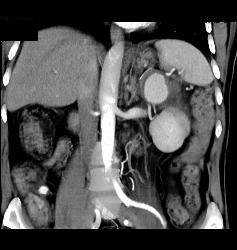

Page Kidney With Bleeding Splenic Artery Aneurysm- See Sequence